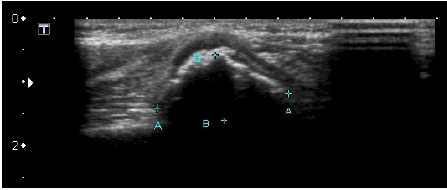

Criança de 5 anos, feminina, apresenta no exame físico área de entumescimento de partes moles no aspecto medial do terço proximal do úmero esquerdo com sinais de estar fixa aos planos profundos e livre em relação à pele e ao subcutâneo, sem sinais flogísticos e quase indolor.

Segue-se imagens de US e Rx do segmento corpóreo.